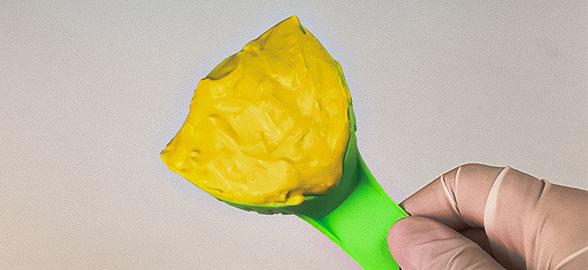

Tomar una impresión dental precisa es un paso crítico para asegurar el éxito de cualquier restauración.

La toma de impresiones dentales es un procedimiento esencial en odontología, ya que permite obtener un registro preciso de la anatomía bucal del paciente para la confección de prót